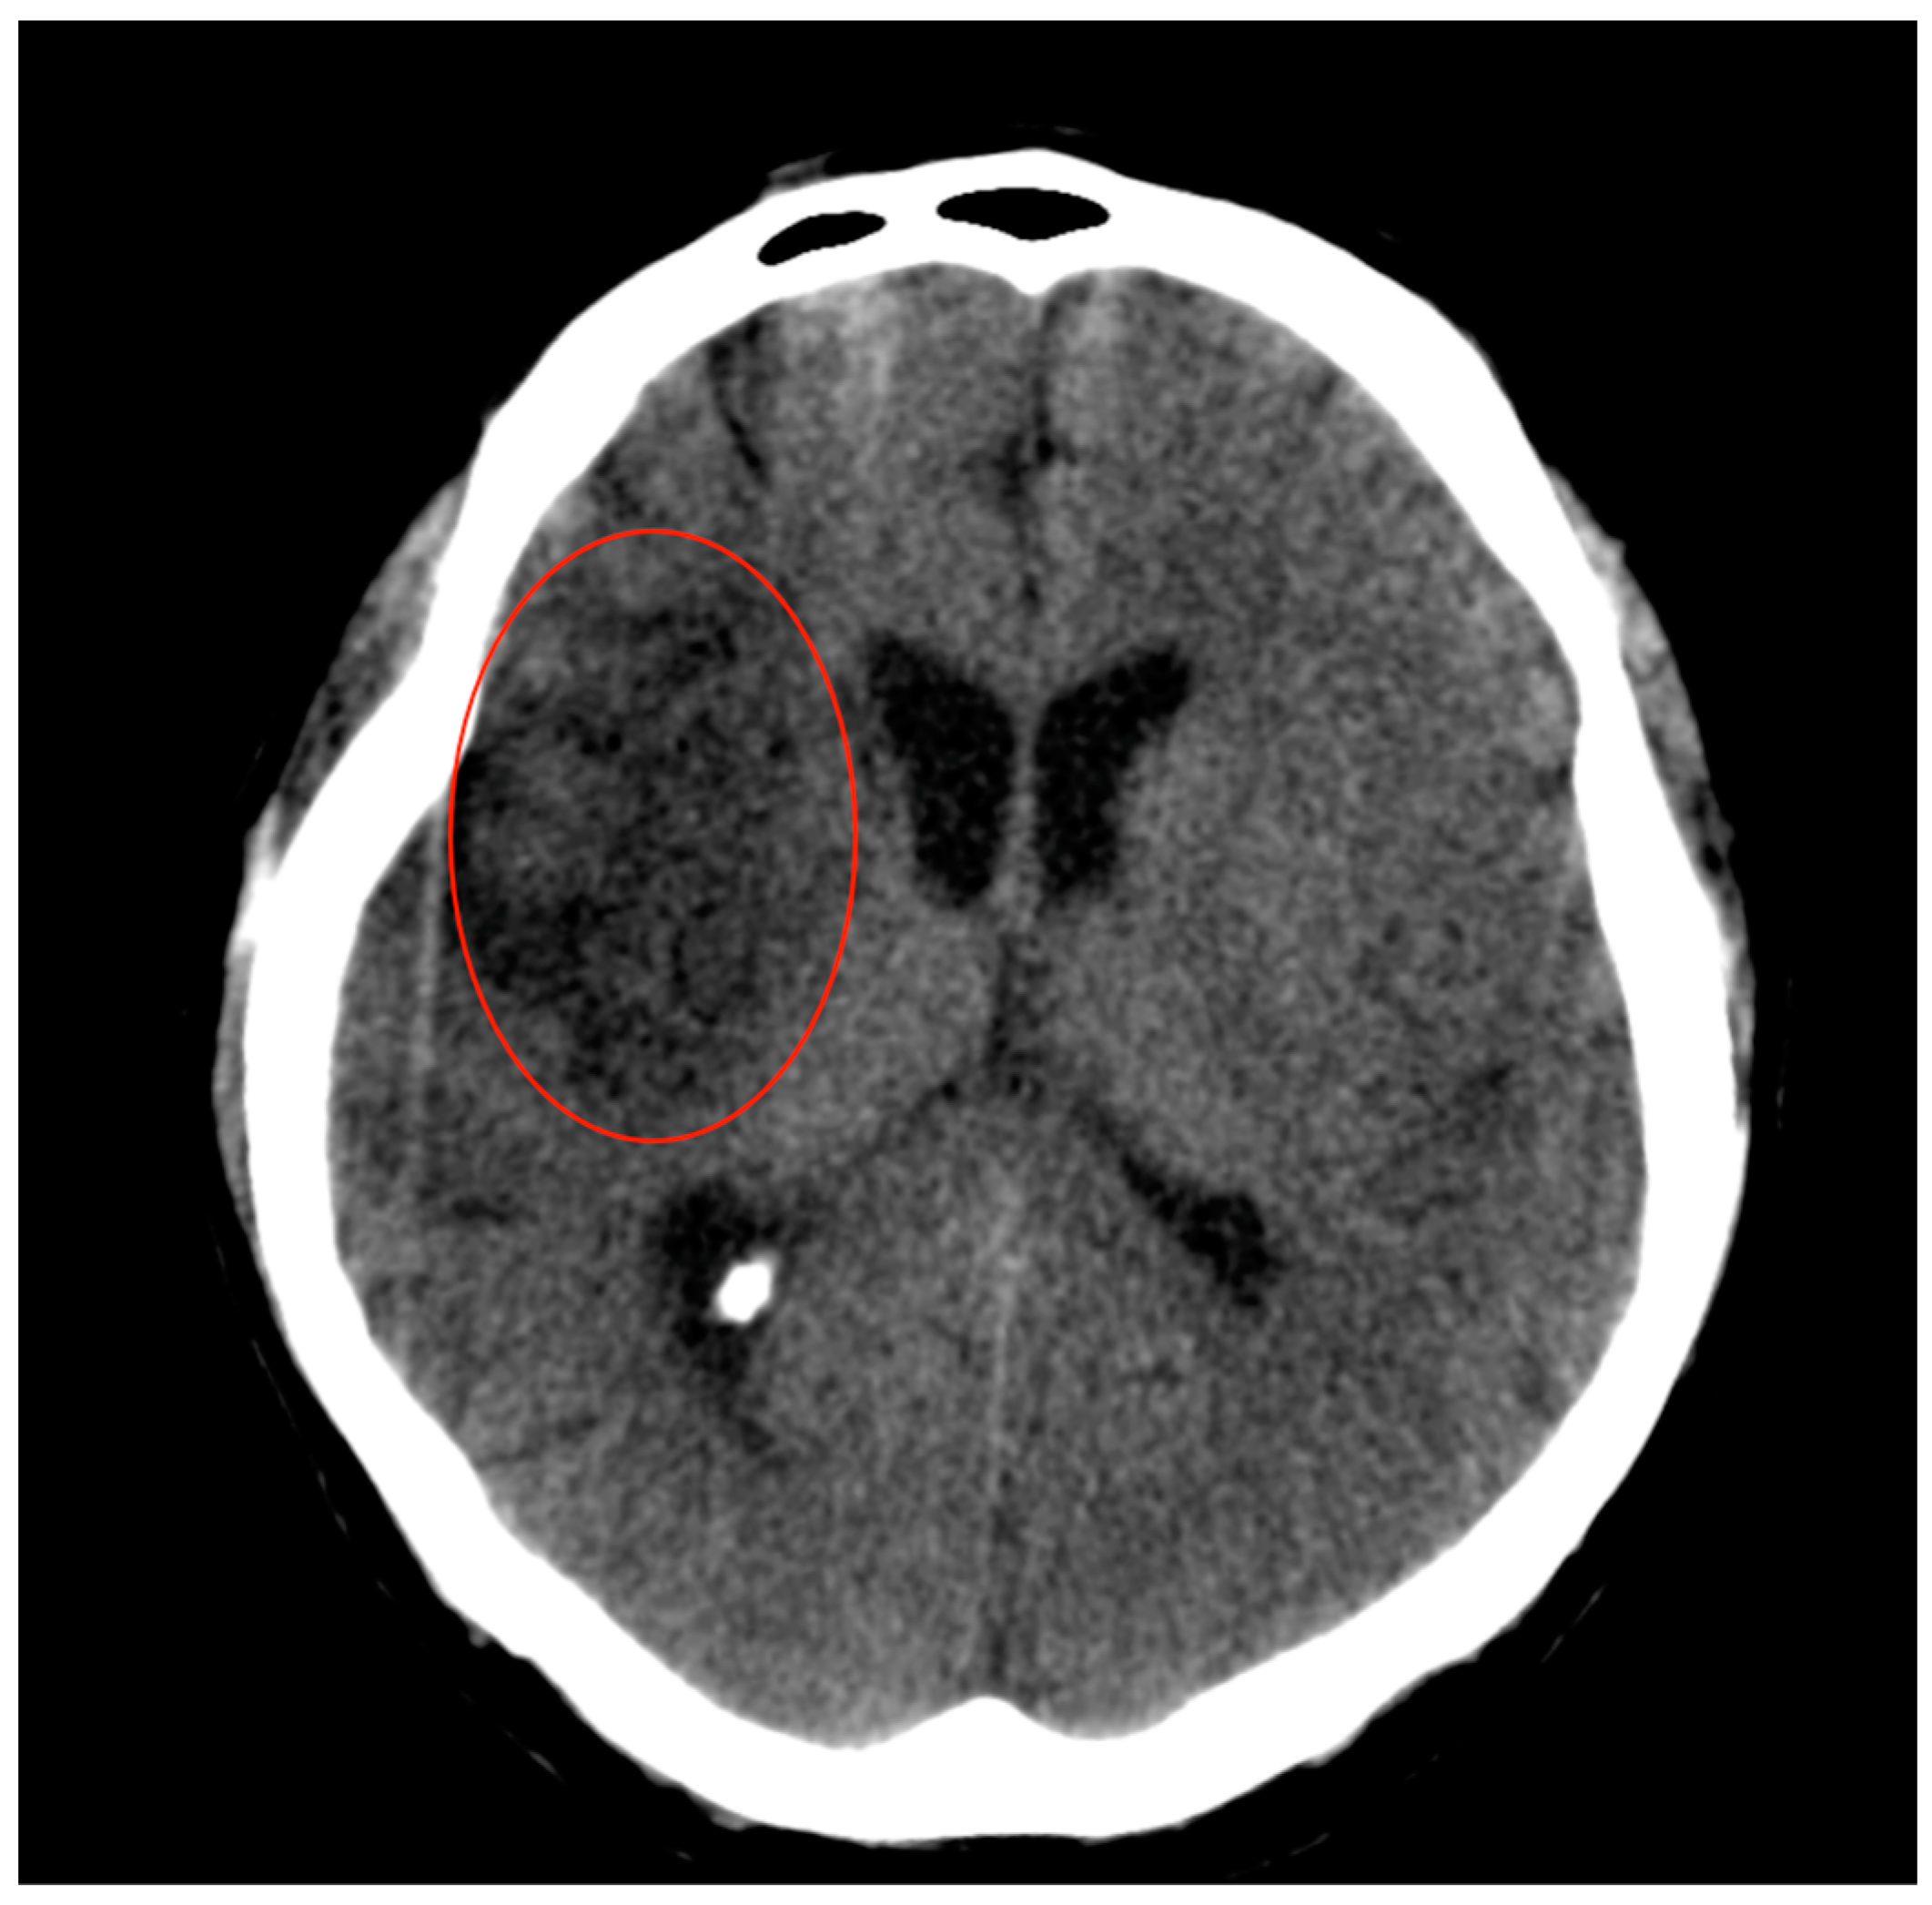

2.1. Case Presentation